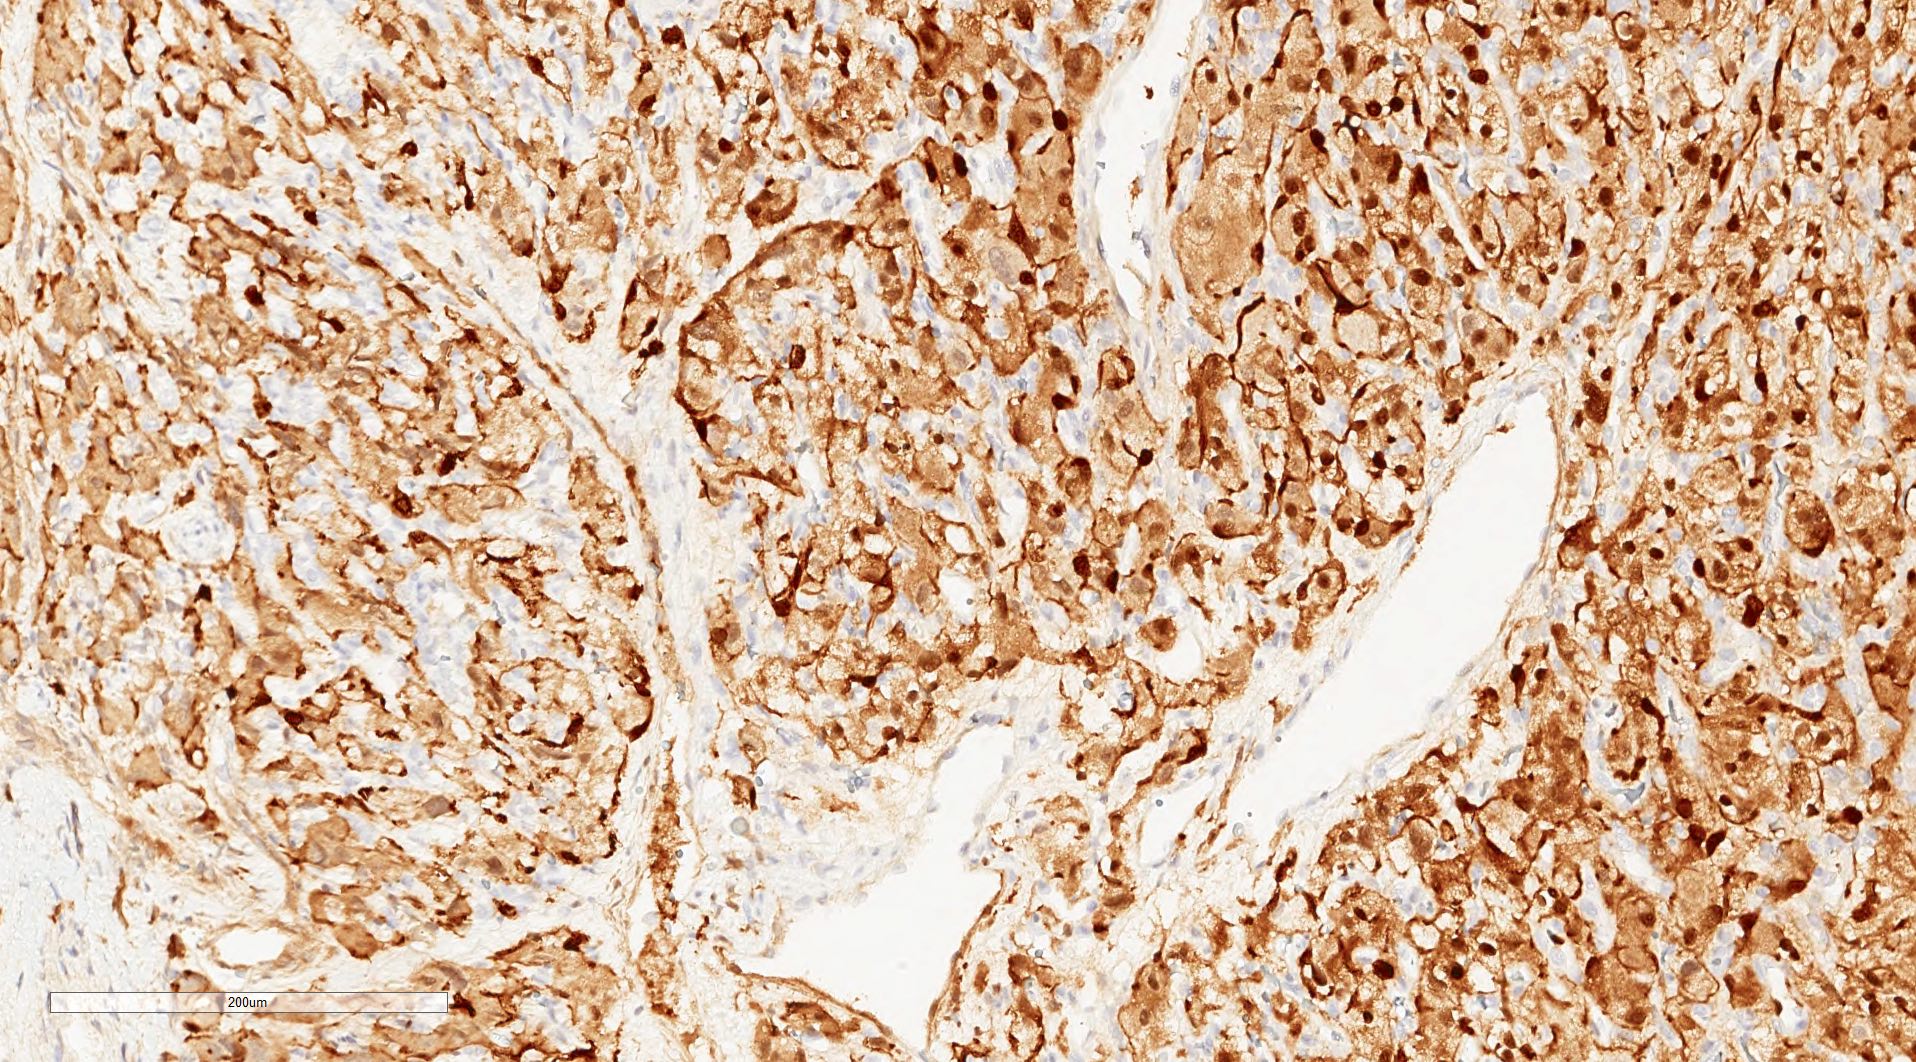

- Classic histologic morphology: monomorphic cells with abundant eosinophilic / amphophilic cytoplasm arranged in a nested / zellballen pattern and separated by fibrovascular septa with sustentacular cells

- Typical morphology: epithelioid cells with abundant, eosinophilic / amphophilic, granular cytoplasm and round / ovoid, vesicular / salt and pepper nuclei, arranged in a nested / zellballen pattern and separated by fibrovascular septae with sustentacular cells (Am J Surg Pathol 2004;28:94, World J Clin Cases 2014;2:591, Endocr Pathol 2022;33:90)

- May have focal pleomorphism, nuclear hyperchromasia, low mitotic activity or clear cytoplasm

Microscopic (histologic) images

Contributed by Theodorus H. van der Kwast, M.D., Ph.D., Michelle R. Downes, M.D., Debra L. Zynger, M.D. and David Cohen, M.B.B.Ch., M.D.

- Microscopic description: This specimen shows an unencapsulated, monomorphous population of round tumor cells in a nested / zellballen pattern with delicate vascular septa and intervening extravasated red blood cells. It predominantly involves the lamina propria of the bladder but in 1 tissue piece clearly involves muscularis propria. The tumor cells have abundant amphophilic cytoplasm and vesicular chromatin with occasional small nucleoli. There is no necrosis, diffuse growth pattern or vascular space invasion identified. The mitotic count is (maximally) 1/10 high power fields. Immunohistochemistry shows the tumor cells to be positive for GATA3 with strong and diffuse expression of synaptophysin and chromogranin, as well as retention of SDHB staining. The tumor cells are negative for AE1 / AE3, HMWK and p63. The Ki67 proliferation index is < 1%. S100 shows faint nuclear and cytoplasmic staining with occasional sustentacular cells identified.

- Microscopic description: Sections show unremarkable surface urothelium with a lesion in the deep lamina propria comprised of large eosinophilic cells with hyperchromatic, focally enlarged nuclei with occasional intranuclear inclusions. A fine vascular plexus is identified in some areas. Necrosis and hemorrhage are not identified. Mitotic rate = 1/10 high power fields (field of view [FOV] = 0.55 mm). The lesion extends to the cauterized base of the specimen. Immunostains confirm the lesion expresses synaptophysin, chromogranin and GATA3. SDHB is retained. AE1 / AE3, CD45, p63 and NKX3.1 are negative.